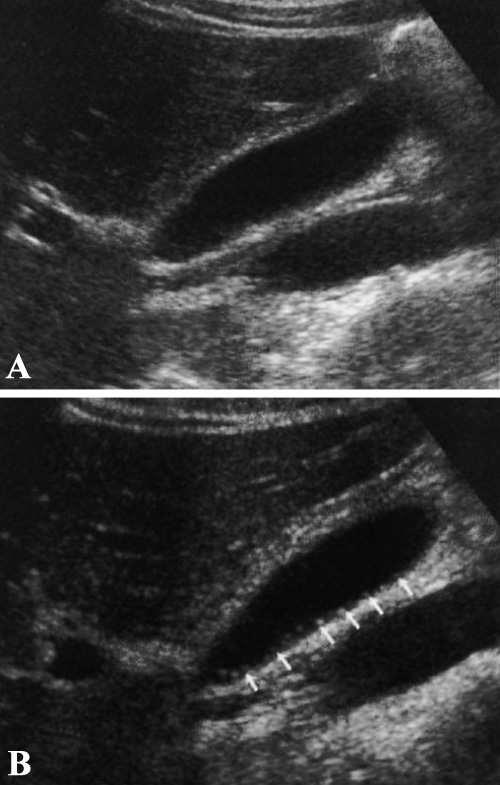

Застойная желчь формируется из билирубината кальция и кристаллов холестерина, которые содержаться в желчи. Ультразвуковая картина застойной желчи характеризуется эхом умеренной интенсивности. Застой желчи, обусловленный перееданием, обструкцией желчевыводящих протоков на уровне желчного пузыря, пузырного протока или общего желчного протока, является основной причиной образования застойной желчи (фото 10). Застой желчи (билиарный сладж) может указывать на какое-либо сопутствующее заболевание, однако не является специфическим признаком.

Фото 10. Застой желчи (билиарный сладж). А – УЗИ в продольной проекции, пациент в положении лежа на спине. В – УЗИ в продольной проекции того же пациента в положении лежа на левом боку. Ультразвуковая картина демонстрирует подвижный эхогенный застой желчи, форма которого меняется при перемене положения тела пациента